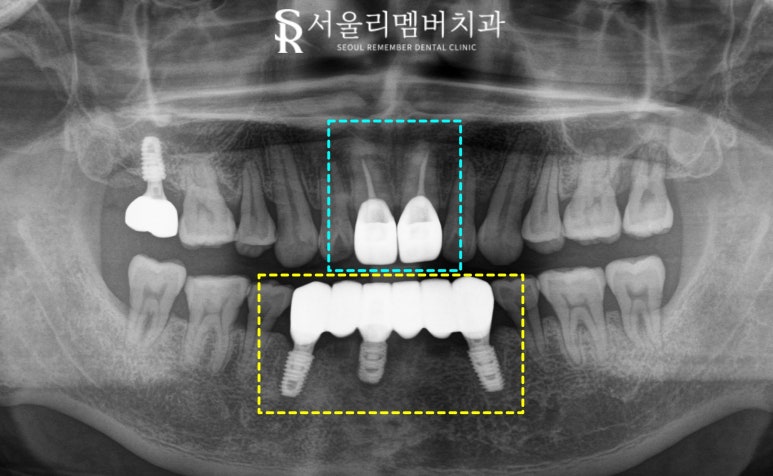

그리고 파노라마와 3차원 CT 사진을 통해

33, 41, 43번 부위에 픽스처를 식립하기로 했습니다.

이후 임플란트 위에

브릿지 형태의 보철물을 제작하여

3개의 픽스처만으로 6개의 치아 기능을

회복하도록 한 것이죠.

또한 이 과정 중간에

상악 앞니 11, 21번은

신경치료(근관치료)를 진행했습니다.

치아 내부의 감염된 신경을 제거하고

깨끗하게 소독한 후

밀폐하는 술식으로

이때는 이가 약해지므로

크라운으로 덮어씌워

심미-기능을 모두 회복해 줘야 됩니다.

2025.05.23

보철이라는 것을

말하지 않으면 알 수 없을 만큼

매우 뛰어난 심미성을 가진

크라운이 수복된 것을 확인할 수 있습니다.

전치부 치료에서 제일 중요한 것은

바로 '심미'인 만큼

임플란트 크라운과 일반 크라운 모두

환자의 기존 치아 색과 모양에 맞춰 제작했으며

잇몸 라인과의 조화, 인접 치아와의 균형을

종합적으로 고려하여 자연스러운 미소를 완성했습니다.

치료 기간 : 2024.11.16 ~ 2025.05.23